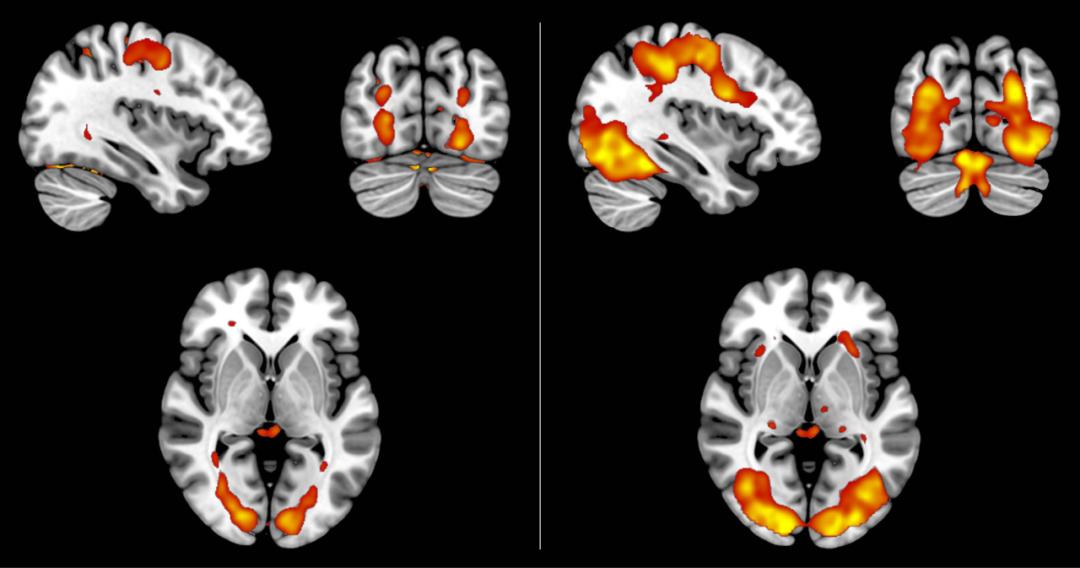

为了深入理解大脑图区分现实与想象的内在机制,研究人员重新分析了此前一项脑部扫描的研究数据,其中35名被试对各种图像,如浇水壶和公鸡等,进行了生动的想象和真实的感知。他们的发现与其他研究结果相符,即在两种情形下视觉皮层中的活动模式极其相似。戴克斯特拉指出:“生动的想象更接近于感知,但模糊的感知是否更近似于想象,这一点我们还不清楚。”有迹象表明,观看模糊图像可能会产生类似于想象的模式,但差异并不显著,这一现象仍需进一步的研究。

扫描结果显示,无论是想象的还是感知的图像,都触发了类似的大脑活动模式,但是对于想象中的图像(图左),信号相对较弱。